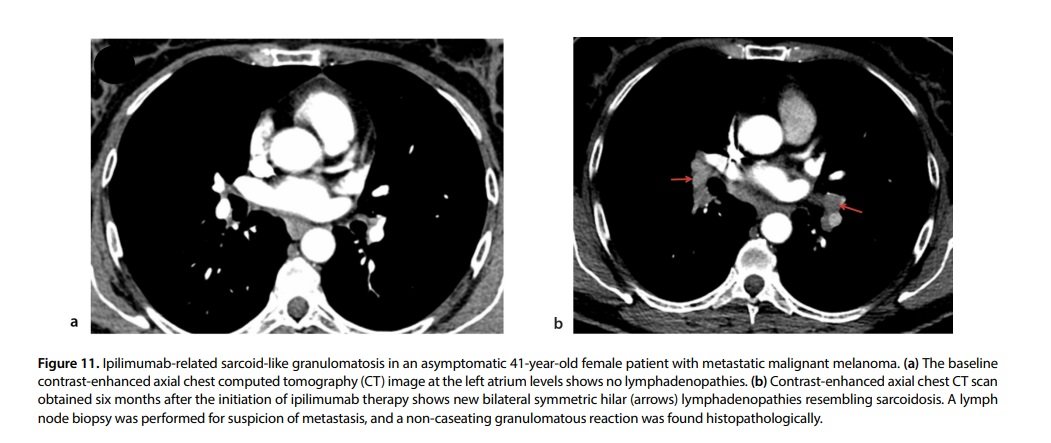

Sarcoid-like granulomatosis (SLG) is an atypical presentation of DILD and is usually associated with ICI therapy. SLG is characterized by histopathological and imaging features identical to sarcoidosis and includes enlarged lymph nodes and perilymphatic lung nodules.